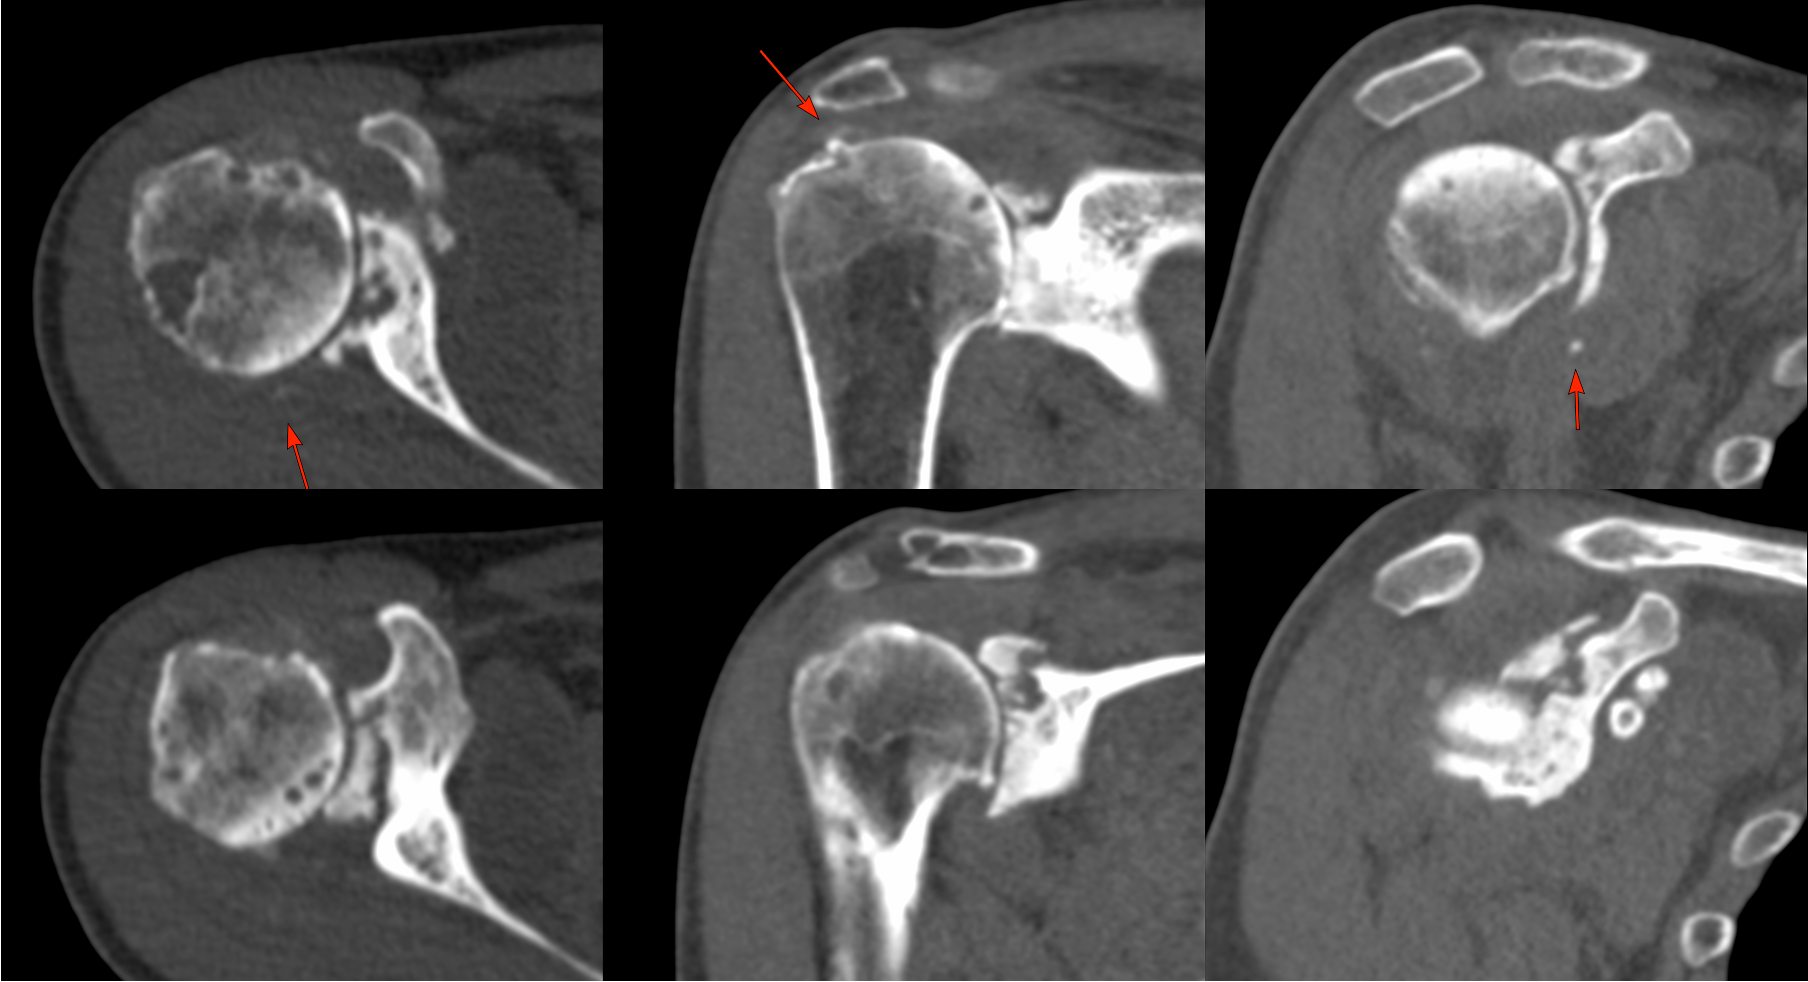

MRI showed a destructive arthropathy, as did a CT scan. Neuroarthropathy was ruled out with an MRI cervical spine.